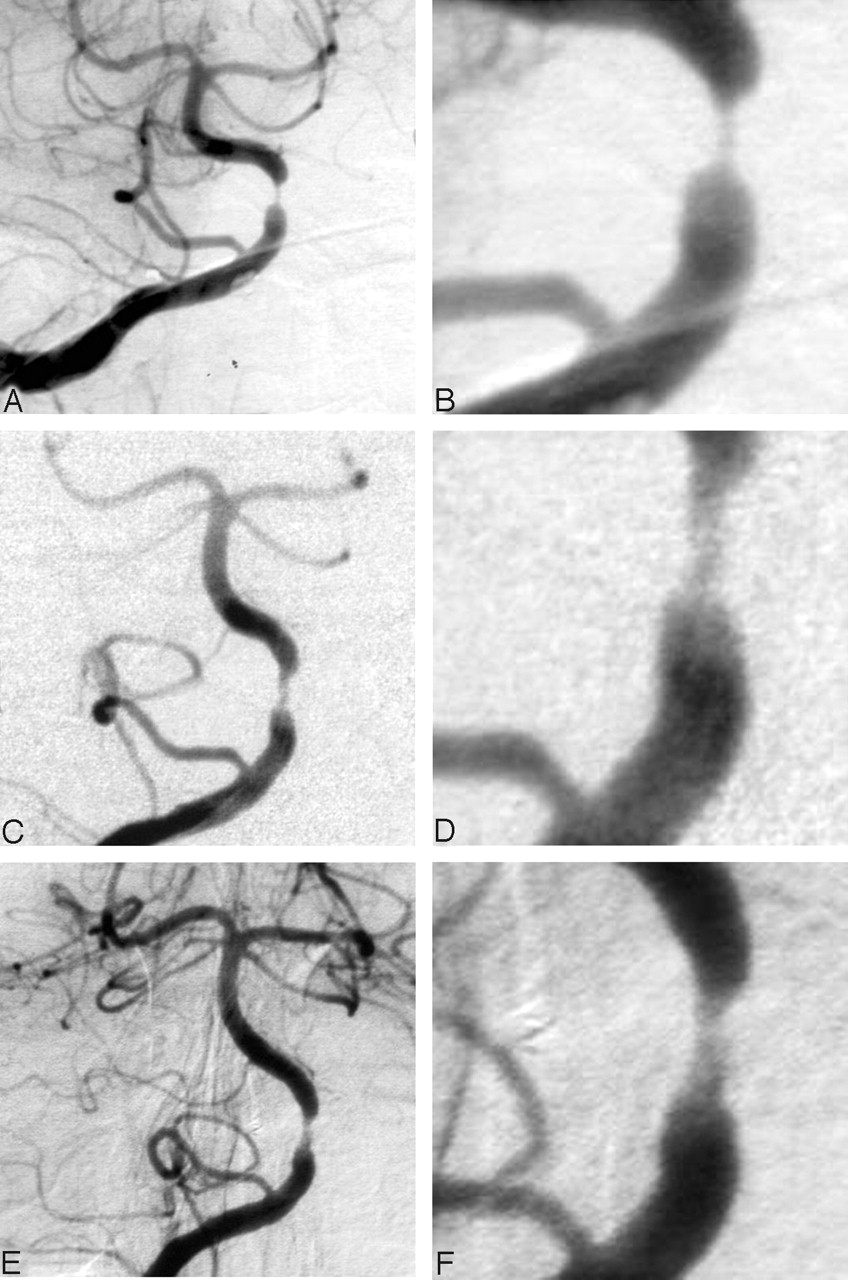

A number of explanations may account for the reduced incidence of strokes, even in patients with residual stenoses of >50% at the completion angioplasty. The main goal of the angioplasty is to improve blood flow. Some of these lesions may manifest symptoms only after they become extremely tight, and even relatively minor corrections in the degree of stenosis may improve symptoms and outcomes. Flow is proportional to the fourth power of the radius of the vessel. This means that the flow is approximately doubled when the radius is increased by 20% or the diameter by 10%, so that small increases in the luminal diameter may result in large increases in the flow. Another possible explanation for this observation is that remodeling may occur in the stenotic region as the angioplasty site heals. We did not routinely perform angiographic follow-up on our patients; however, in some cases (especially earlier in our experience), we did have angiographic follow-up and observed a mild reduction in the severity of residual stenosis or remodeling that occurs (Fig 3). We also evaluated outcomes in the subset of 11 patients whose postangioplasty angiograms showed evidence of dissection. Importantly, no strokes or TIAs occurred in this group during follow-up.

This 61-year-old woman had repeated vertebral basilar TIAs while receiving warfarin.

A and B, Anterior pretreatment right vertebral artery angiograms (magnified image in D) show severe stenosis of the proximal basilar artery.

C and D, Anterior right vertebral artery angiograms obtained immediately after angioplasty show improvement in the stenosis but continued moderate luminal narrowing.

E and F, Angiograms obtained 2 months after angioplasty show mild improvement in the stenosis with remodeling. At last follow-up (60 months), the patient did not have additional symptoms.